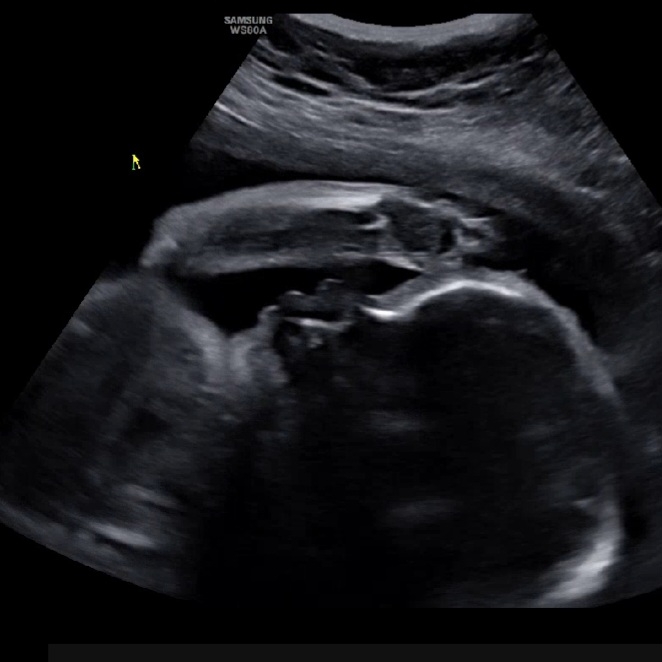

전치태반 확정!

둘째까지는 제왕절개 생각도 안해봤는데 셋째는 전치태반 확정! 안전을 위해 제왕절개 하자고 하시네요. 아가는 모두 정상인데 엄마 태반이 문제. 노산은 힘드네요... 무서워하지 말라고 하셔서 노산이라 회복이 더디지 않겠냐고 하니 자연분만이랑 제왕절개 회복은 하루 차이고, 진통없이 출산하는 장점도 알려주셨는데 왜 슬플까요... 늘 팔로 가리고 있어서 옆모습만 보여주는 우리 셋째. 엄마 힘낼께!